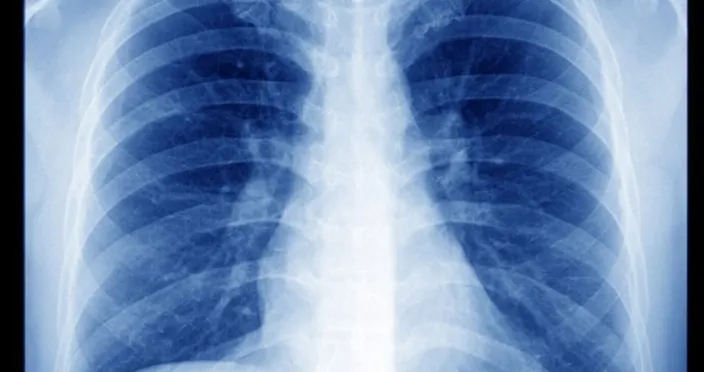

TOMOGRAFİ RÖNTGENDE SIVI GÖRÜLÜRSE VE HASTANIN ŞİKAYETLERİYLE ORANTILIYSA TEŞHİS KONULUR

Akciğer zarının hastalıkları 2ye ayrılır. Bir iltihabı hastalıklar vardır bir de tümör hastalıları vardır. Akciğer zarının kuru ve sulu iltihaplarıdır.Akciğer zarında en ufak bir kalınlık ve su toplanması görüldüğü zaman sıvı alınmalıdır.

Tahlil hem mikrop hem de kanser yönünden incelenir. Mikrop yönünden hem basit mikroplar hem de verem mikrobu incelenmek zorundadır. Çünkü akciğer zarını en çok hastalandıran verem olduğu için bu inceleme yapılmalıdır. Akciğer zarında bir su birikintisi ya da kalınlaşma olduğu zaman veremi düşünmek lazım. Sonra 2. planda kanseri düşünmek lazım sonrada diğer hastalıklar gelir.